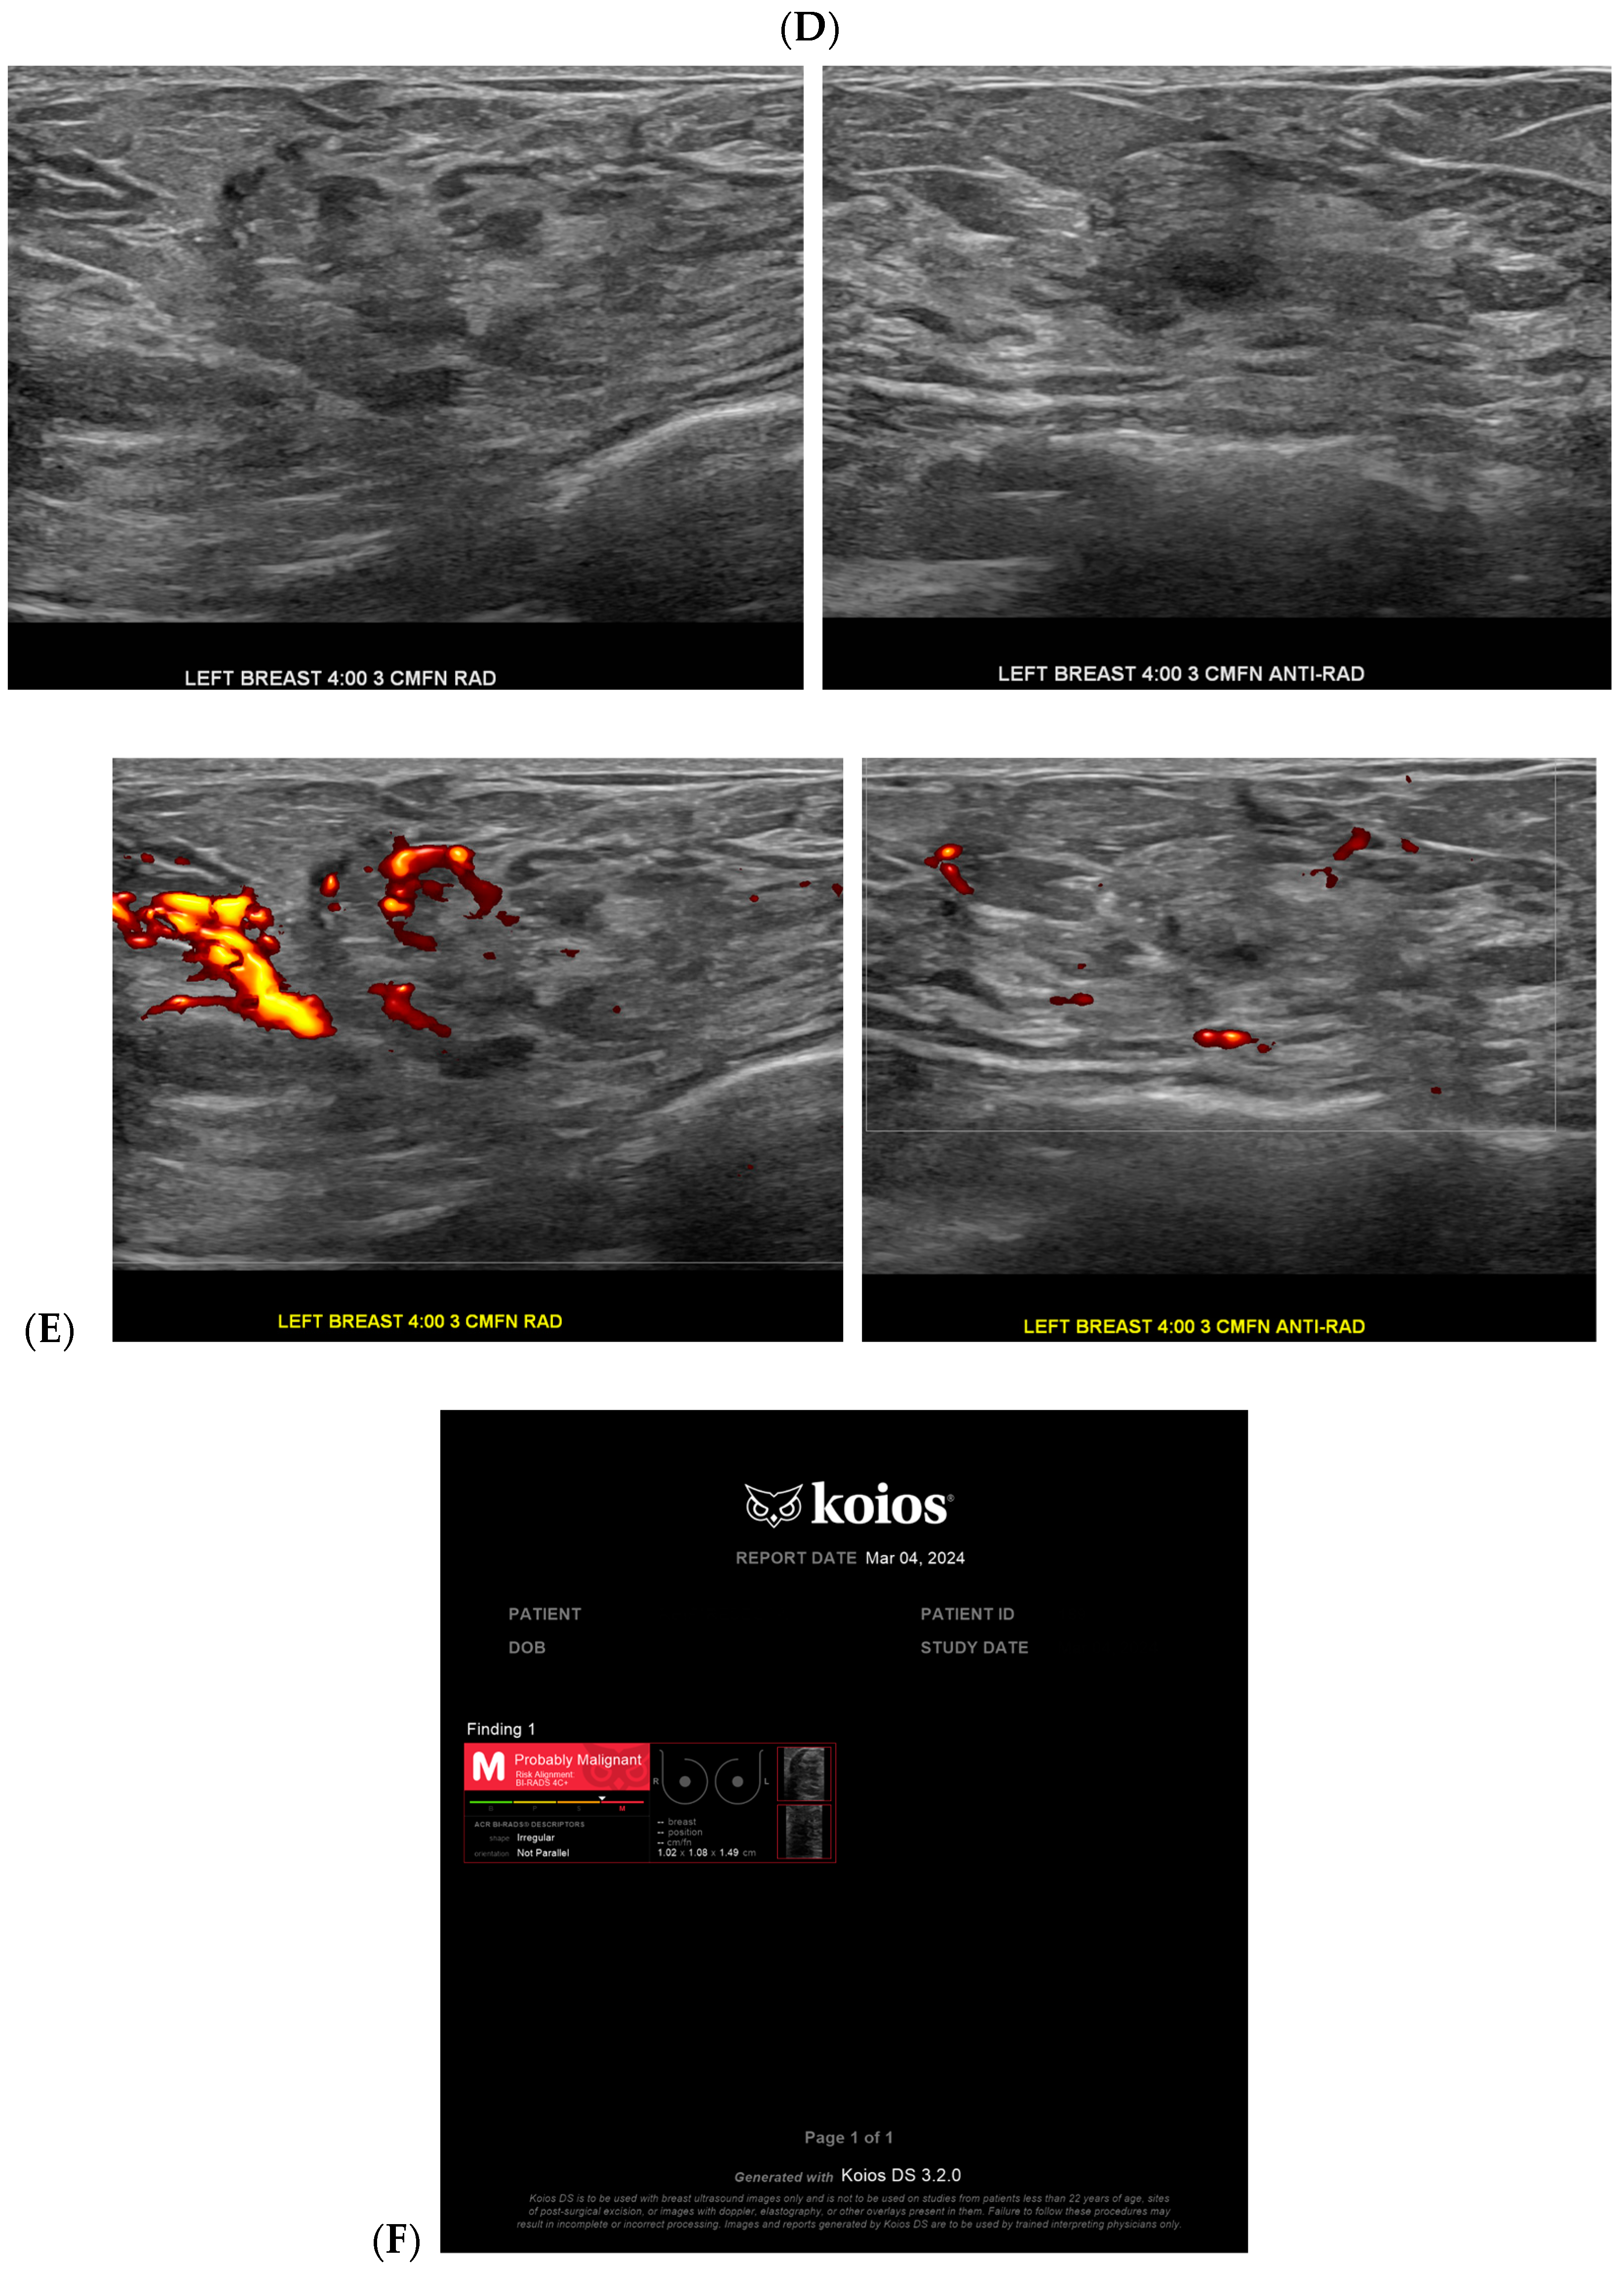

Cancer detection systems typically involve neural networks, machine learning, or deep learning developed from training models to recognize patterns, while diagnostic systems use an additional algorithm to classify [17]. Several CNN models have been developed to correlate ultrasound imaging features of a lesion with the four-classification breast cancer molecular subtypes [42]. Our institution uses Koios, which utilizes machine learning and AI to generate the probability of malignancy of a breast finding by evaluating a region of interest (ROI) selected by a radiologist [3,5]. Ultrasound AI has been found to reduce intra- and interobserver variability and to improve accurate BI-RADS classification of sonographic breast findings [3,5]. Ultrasound AI can also increase CDR [5] and reduce the number of unnecessary biopsies [5,43,44] (Figure 1, Figure 3, and Figure 4).

Figure 4.

A benign finding appropriately classified as benign by artificial intelligence (AI): The patient initially presented for a bilateral screening mammogram and a bilateral screening breast ultrasound. A mammogram revealed benign dystrophic calcifications in the upper outer quadrant of the right breast (A). Correlating with findings on the mammogram, ultrasound revealed a complicated cyst showing posterior acoustic shadowing consistent with fat necrosis (B). The AI program Koios recognized this mass as “Benign” (C). Images obtained from the Icahn School of Medicine at Mount Sinai.